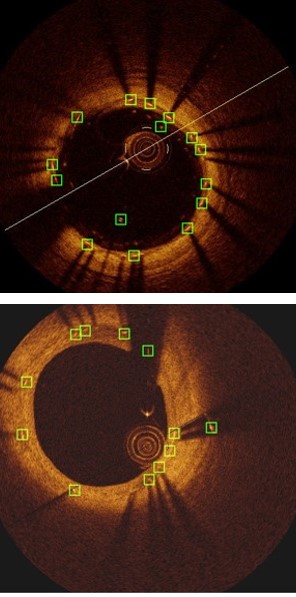

Refer to caption

Figure 3: Strut detection results: (a) Comparison of our method to the existing methods, (b) component analysis of our method.

Table 1 and Fig. 3(b) show the detection results of our method at individual stages. Fig. 5(a) shows the two example detection results with various thickness coverage. The Local-Network shows the higher recall while Global-Network achieved better precision results (as shown in Fig. 5(c) and Fig. 5(d)). As exemplified in Fig. 5(e), the proposed method integrated both Local Network and Global-Network and achieved a better consistent performance in recall and precision.

Table 1, Fig. 3(b) and Fig. 5 compared the main components of our method individually to quantify their contributions to the final detection results. These results demonstrate that Local-Network has higher recall and we attribute this to the usage of patch-based network to detect all the potential strut candidates. In contrast, Global-Network achieved higher precision for its ability by adding global context, e.g., appearance information, as part of the learning process, which ensures all the detected struts are consistent with the shape of the stent. Table 1, Fig. 3(b) and Fig. 5 also show the advantages from our combination which integrates complementary detection results produced at individual components.